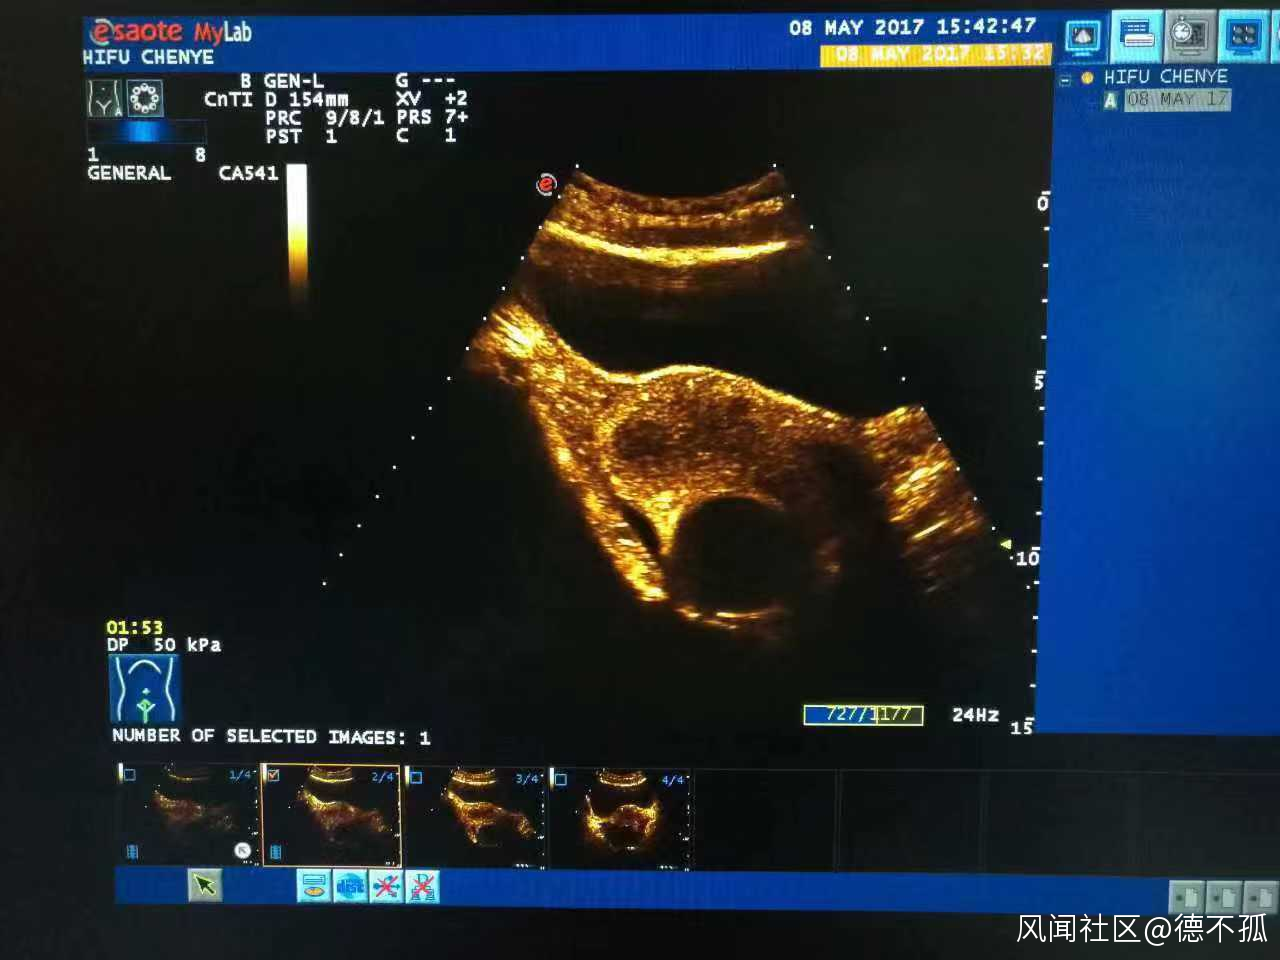

高強度聚焦超聲治療系統(HIFU)是一種綠色、非侵入性的治療技術,它利用超聲波的可聚焦性和可穿透性,將體外低強度超聲波聚焦到患者體內病灶,在焦點處瞬間產生高温(60℃-100℃),使病灶組織發生不可逆的凝固性壞死,而正常組織不受損傷,從而實現不開刀、不流血、保留組織器官及其結構功能的“無創治療”。有人形象地稱此為“隔山打牛”式的治療。

據六院超聲醫學科主任醫師姜立新介紹,目前在HIFU治療的眾多腫瘤適應症中,子宮肌瘤治療獲得了較明確的療效。“以往如子宮肌瘤需要等待手術指徵符合時才可治療,若患者有備孕需求,或已處於圍絕經期,則會造成一定困擾。通過HIFU技術,半年內子宮肌瘤即可縮小,患者可正常懷孕。”